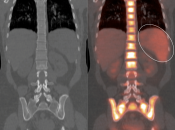

Normal Skeletal Uptake

Mild to moderate FDG uptake can be normally seen within red marrow, most commonly affecting the vertebral bodies, sternum, pelvis, and proximal long bones (it is not unusual to see fairly prominent uptake within the proximal half of the femurs). This red marrow uptake can be quite heterogeneous at times, yet still normal.

Diffuse Skeletal Uptake:

Intense and diffuse reactive marrow uptake is frequently seen as the result of chemotherapy and/or colony stimulating factors (discussed in detail, here).

If rather diffuse and intense uptake is noted without a history of recent chemotherapy or colony stimulating factors, be suspicious of infiltrating disease such as lymphoma.

Focal Skeletal Uptake:

Focal skeletal uptake warrants extremely close assessment of the co-registered CT images to exclude malignancy. Other etiologies of focal skeletal uptake include fracture, arthropathy, infection and several benign bone lesions.